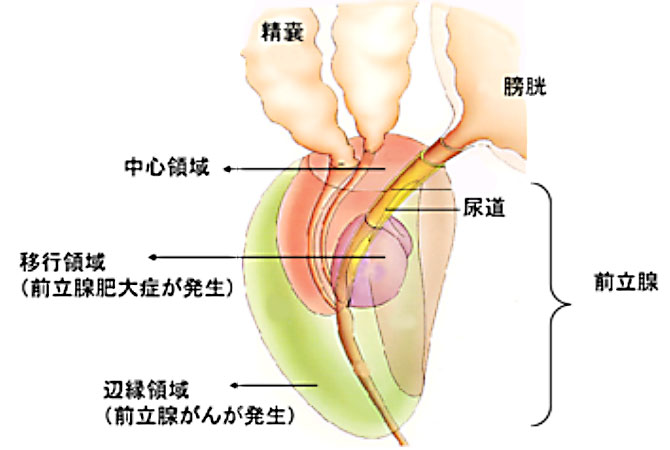

対象となる病気 前立腺がん 診療紹介 金沢医科大学 泌尿器科学

前立腺がん 泌尿器科の病気について 名古屋大学大学院医学系研究科

前立腺がん 腎泌尿器疾患のキーポイント 三重大学大学院 医学系研究

前立腺がん 泌尿器科の病気について 名古屋大学大学院医学系研究科

泌尿器疾患 前立腺癌の診断と治療 医師修学資金貸与制度を有する

前立腺がんについて 成田市公津の杜 なかまち泌尿器科クリニック

前立腺がん 泌尿器の病気について 患者さんへ 長崎大学病院 泌尿器

泌尿器科がん 前立腺がん 岡山大学大学院医歯薬学総合研究科泌尿器

特集2 前立腺がん 早くみつければ こわくない 全日本民医連

前立腺がんの症状 がん治療に免疫の力をプラス がん免疫療法情報ガイド

前立腺がん 腎泌尿器疾患のキーポイント 三重大学大学院 医学系研究